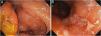

In 2022, he had simultaneous worsening of AD and HS: fistulized nodules on the face, abdomen, axillae, and buttocks (Fig. 2). He had intense pruritus and exudative erythematous-squamous lesions, on the face, hands, thighs, and feet. The IgE level was 1006 kU/L and fecal calprotectin was >3000 µg/g. DLQI was 18 and SCORAD was 65.4. An ileocolonoscopy showed deep ulcers and inflammation in the right colon (Fig. 3).

Upadacitinib 15 mg/day was started with complete improvement of the skin lesions (Fig. 2). The patient showed clinical remission of CD, with fecal calprotectin normalization at 35 µg/g and ileocolonoscopy showing endoscopic remission (Fig. 4).